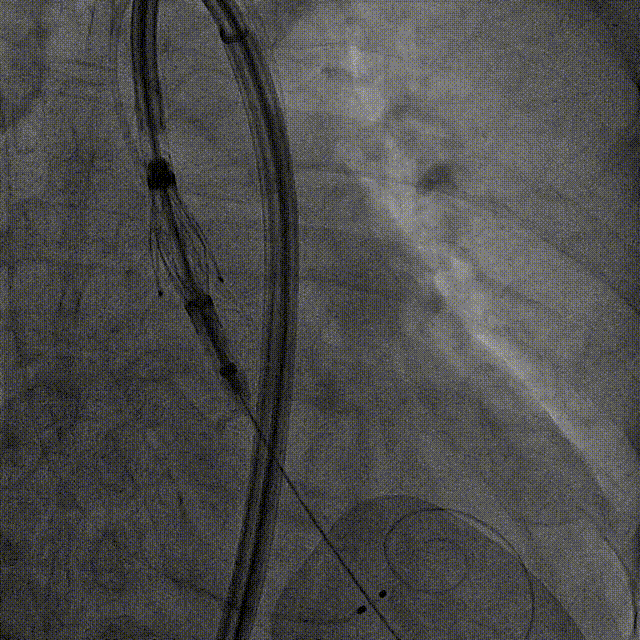

术前右窦中心造影

大鞘植入

瓣膜调弯解离

定位键窦对齐验证

定位键入窦验证

深度检查

一键释放

后扩后造影